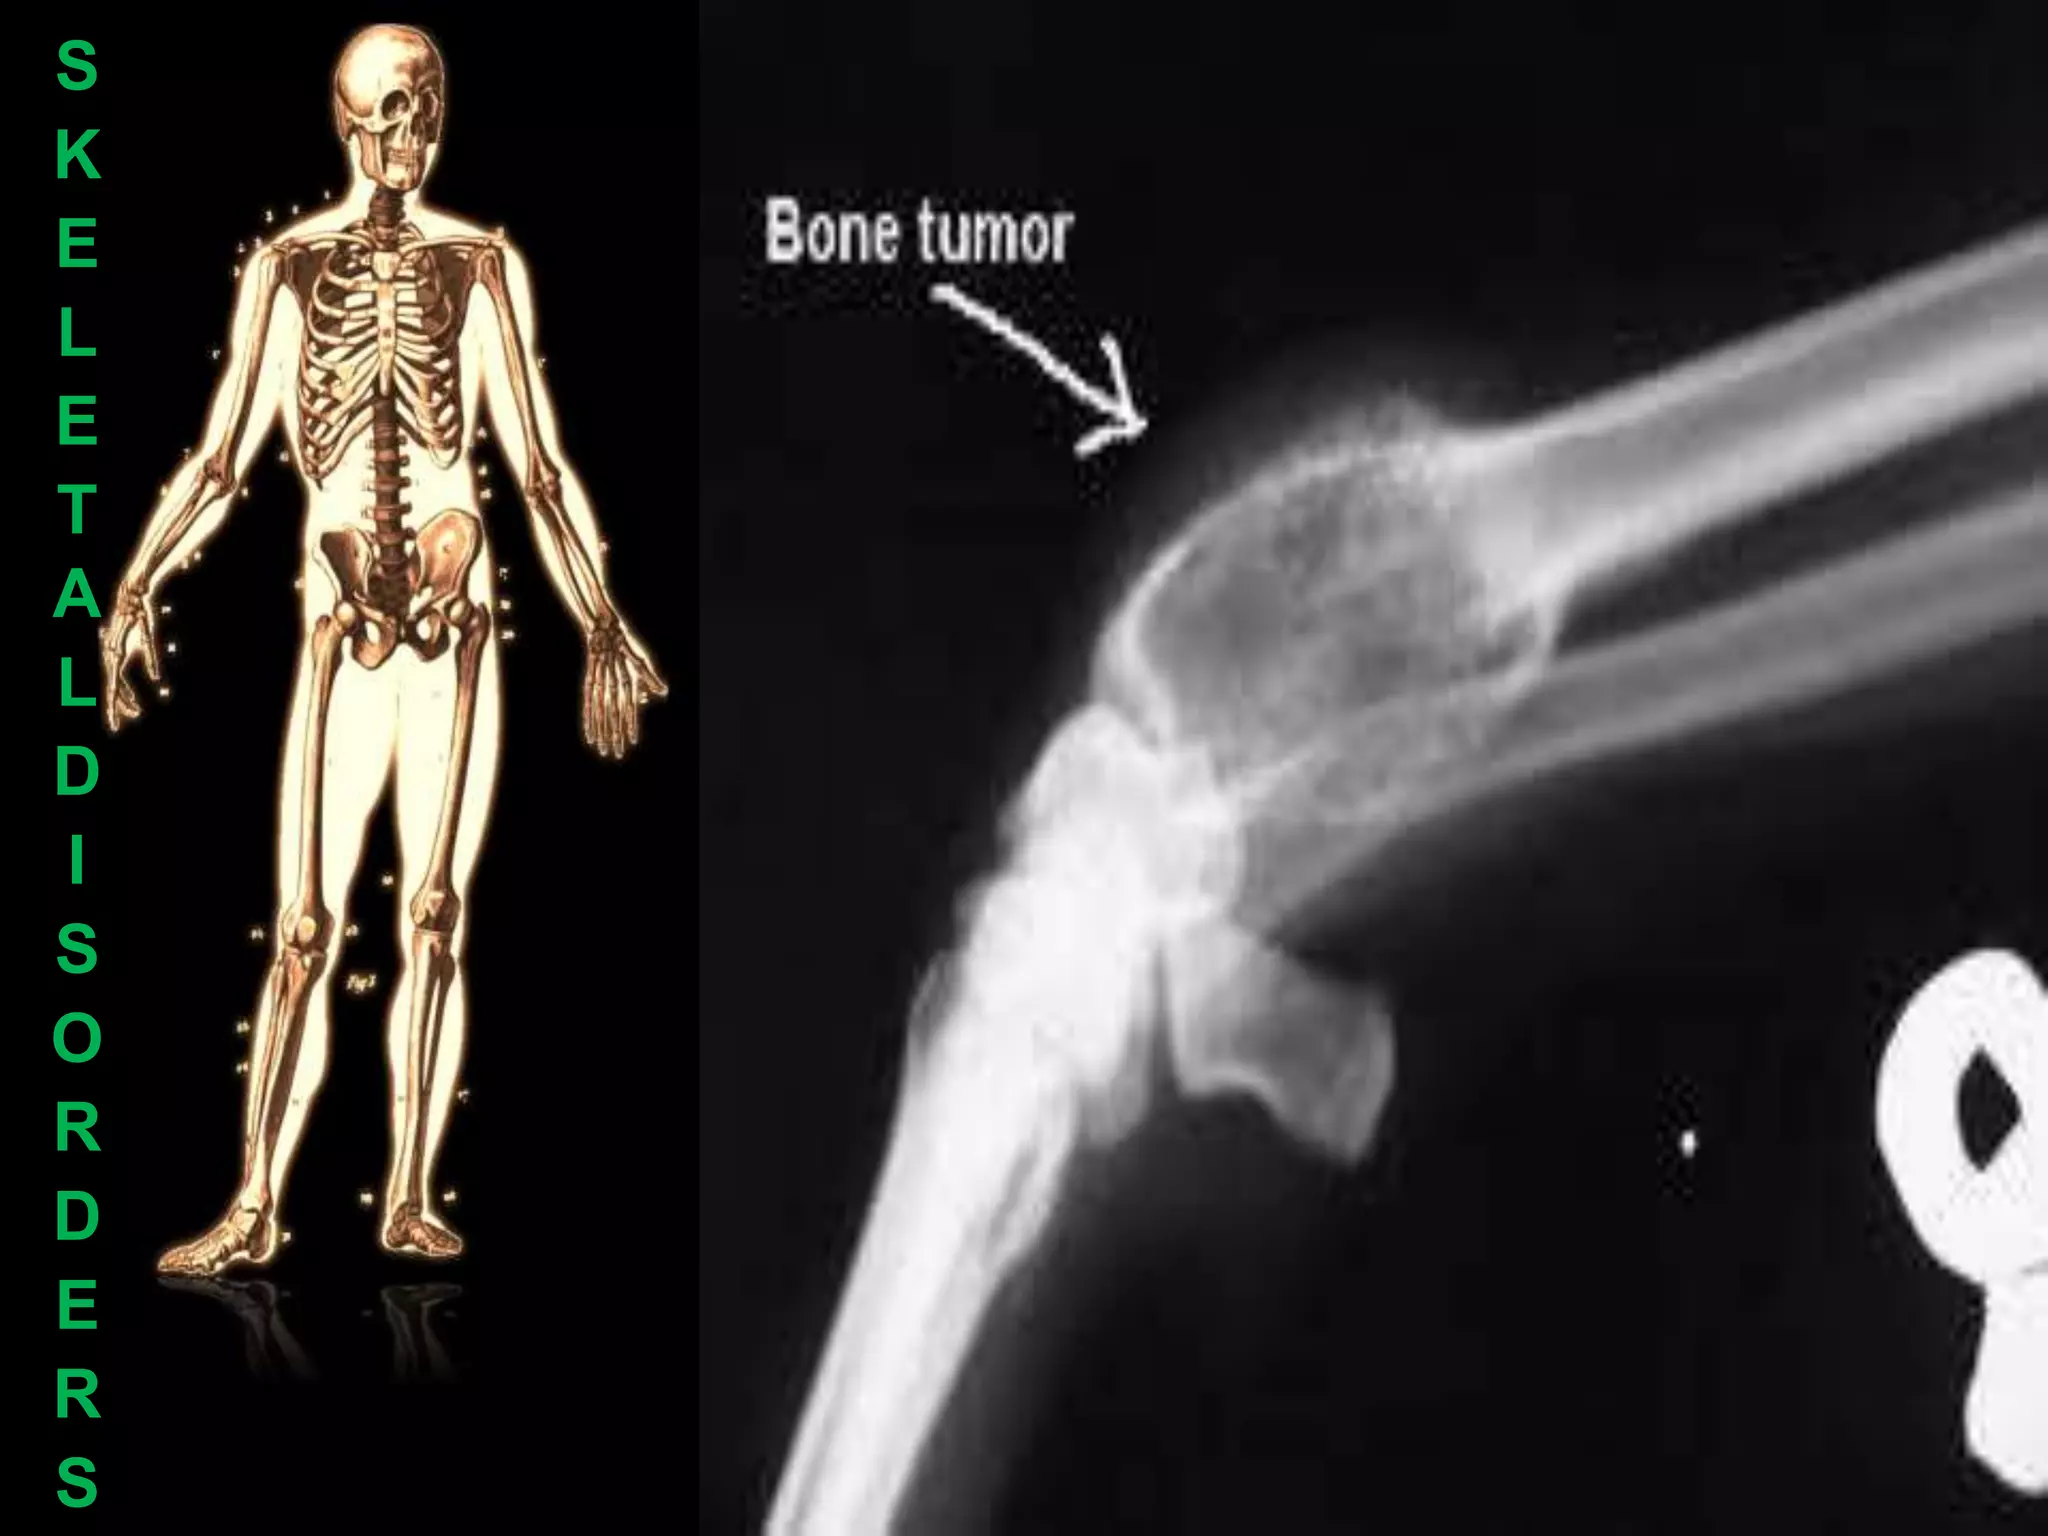

E   Bone Cancer

E     Bone cancer may occur

as a secondary cancer

D   example, prostate cancer

R   Damage to stem cells

D   (the cause of leukaemia).